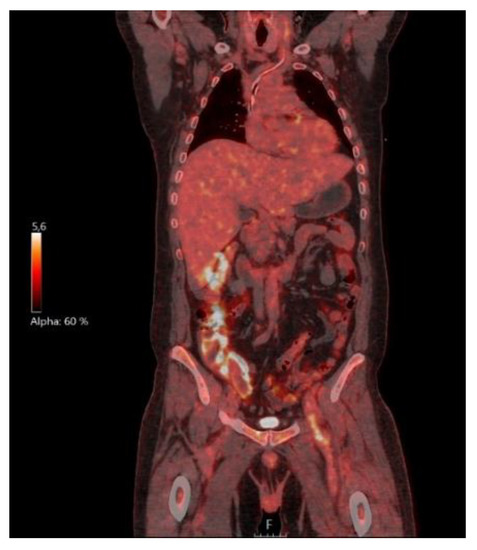

2. Case Presentation